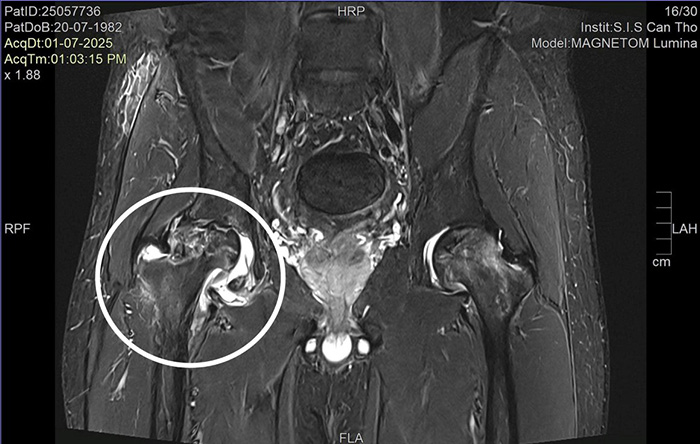

ThS.BS.CKI Nguyễn Trần Duy – Khoa Ngoại tổng hợp Bệnh viện Đa khoa Quốc tế S.I.S Cần Thơ, cho biết: “Kết quả thăm khám và chụp chiếu tại bệnh viện cho thấy anh V. bị hoại tử chỏm xương đùi cả hai bên, với mức độ hoại tử bên phải là độ 3 và bên trái độ 2. Đây mới là nguyên nhân thực sự gây đau nhức vùng hông và hạn chế vận động của anh V. Chúng tôi quyết định phẫu thuật thay toàn bộ khớp háng cho bệnh nhân bằng vật liệu ceramic chống mài mòn cao, giúp kéo dài tuổi thọ khớp háng và cải thiện chất lượng sống”.